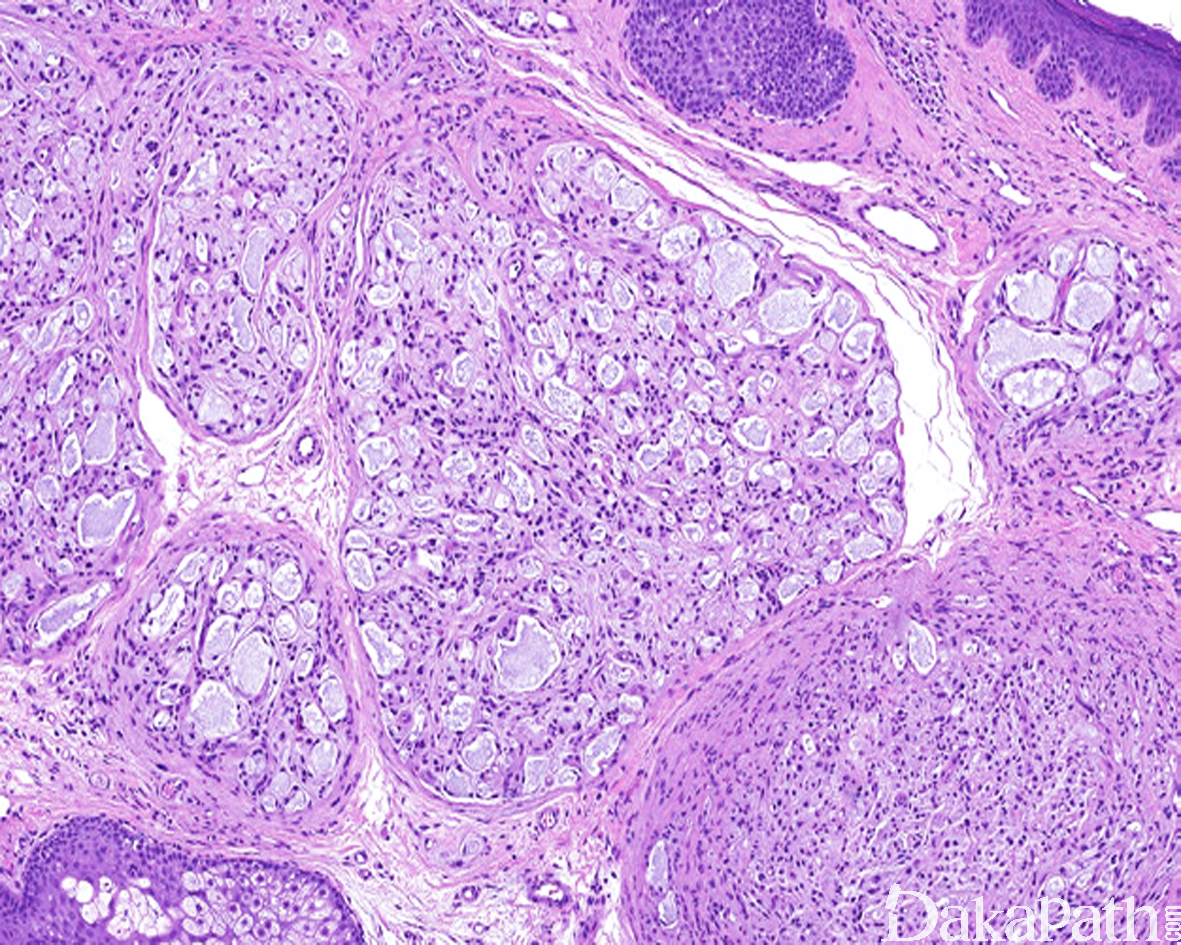

微囊/网状型神经鞘瘤

Microcystic / reticular schwannoma

大部分或完全由位于黏液性基质内的微囊和/或网状结构组成的一种少见组织学类型的神经鞘瘤